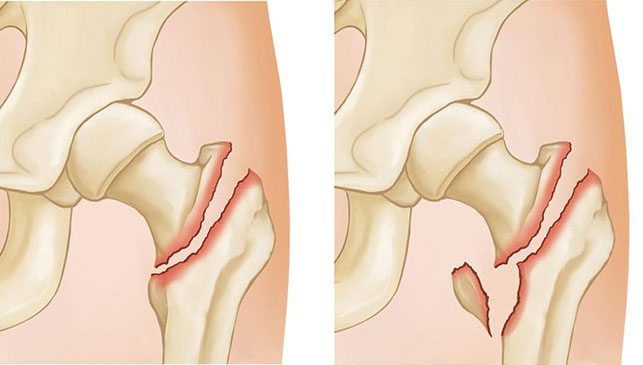

Πρόκειται για κάταγμα του άνω τμήματος του μηριαίου οστού, δηλαδή κοντά στην άρθρωση του ισχίου. Μπορεί να αφορά:

– Κάταγμα αυχένα του μηριαίου (ενδαρθρικό)

– Διατροχαντήριο κάταγμα (εξωαρθρικό)